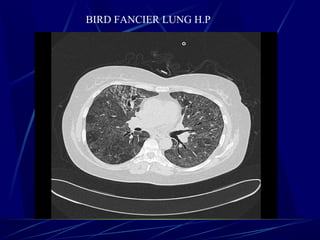

BIRD FANCIER LUNG H.P

Hypersensitivity pneumonitis (HP) (also known as extrinsic allergic

alveolitis) represents a group of pulmonary disorders mediated by inflammatory

reaction to inhalation of an allergen. These may be organic or inorganic

particles (microbes, animal or plant proteins, and certain chemicals) that form

haptens by sensitised individuals.

Depending on the type of precipitant, numerous other more precipitant specific terms

have been used such as:

bird fancier's lung: pigeon fancier's lung

farmer's lung

Cheese workerโ€™s lung

Mushroom workerโ€™s lung

Malt workerโ€™s lung

Maple bark disease

hot tub lung

organic chemicals such as isocyanates found in paint hardeners

from immunosuppresants used in organ transplantation: e.g. sirolimus/everolimus 8